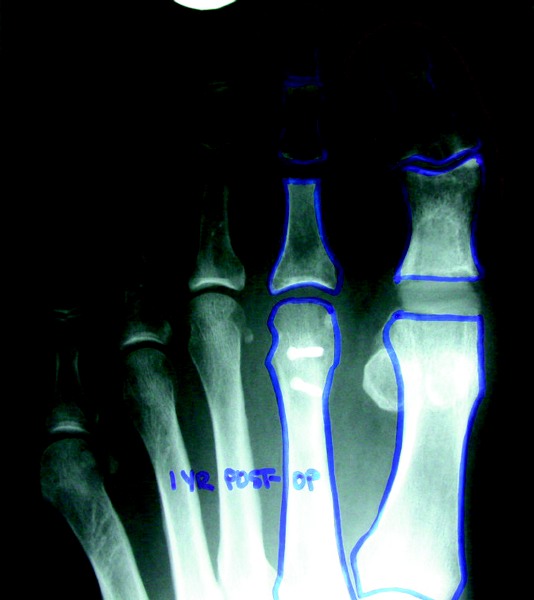

When There Is An Abnormally Long Second Metatarsal Or An Iatrogenic Short First Metatarsal

When patients have an abnormally elongated second metatarsal or iatrogenic short first metatarsal, one may consider performing a Weil osteotomy, which allows shortening of the metatarsal but maintains its ability to bear weight. Surgeons may also consider a digital procedure, whether it is a PIPJ arthroplasty, fusion or arthrotomy with flexor brevis tendon transfer. This procedure is necessary in order to negate the loss of physiological tension of the plantar fascia slip to the second digit that occurs with any shortening metatarsal osteotomy. Failure to perform the digital procedure will most likely result in a floating second toe within a certain time period postoperatively. If there is significant redundant tissue once the digit is realigned on the sagittal plane, one may perform a plantar skin plasty, which enables clinicians to remove an ellipse of plantar tissue from the sulcus of the second digit.